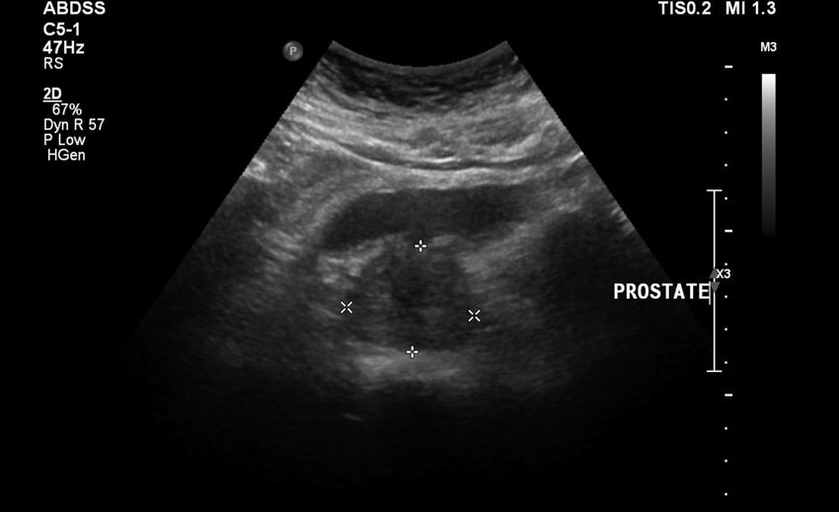

Ils n'ont pas laissé les caoutchoutés en direct calmement, puis les douleurs au bas du dos ont été ajoutées, les tests et les résultats de l'échographie étaient mauvais. Il était littéralement impossible de s'éloigner des toilettes, il y avait une sensation de lourdeur dans l'aine et une douleur constante. Le massage direct de la prostate a été prescrit, ce qui m'a plongé dans la panique. Il a commencé à chercher d'autres méthodes de guérison moins traumatisantes.